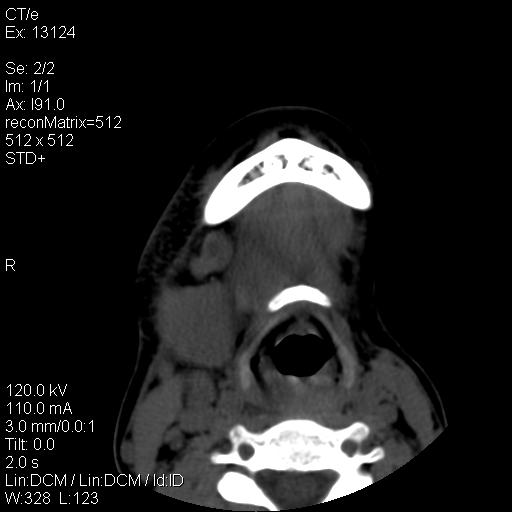

标题: CT18257:女,29岁,右下磨牙痛 [打印本页]

标题: CT18257:女,29岁,右下磨牙痛

女,29岁,右下磨牙痛,因产后2月,故未治疗。现右颌肿痛伴张口困难。请大家看看右侧鼻咽部、口咽部是否

1.考虑右侧下颌区脓肿(牙源性)

考虑右侧下颌区脓肿(牙源性)!支持!

考虑右侧下颌区脓肿。